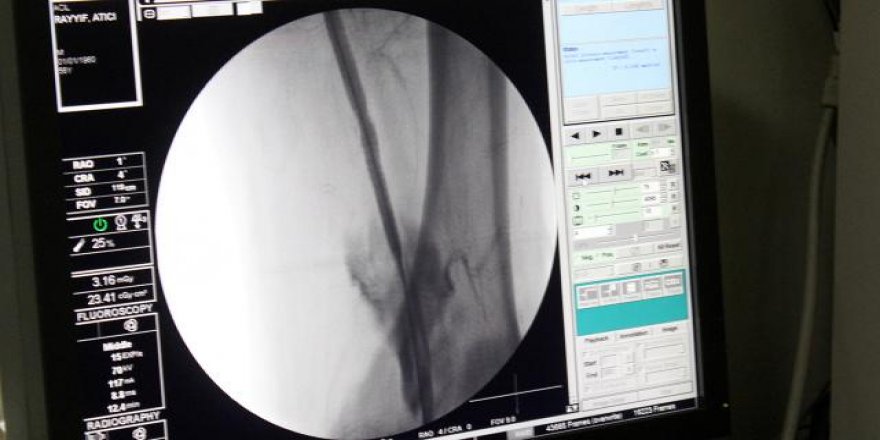

Kalp ve damar sağlığı için nelere dikkat edilmeli